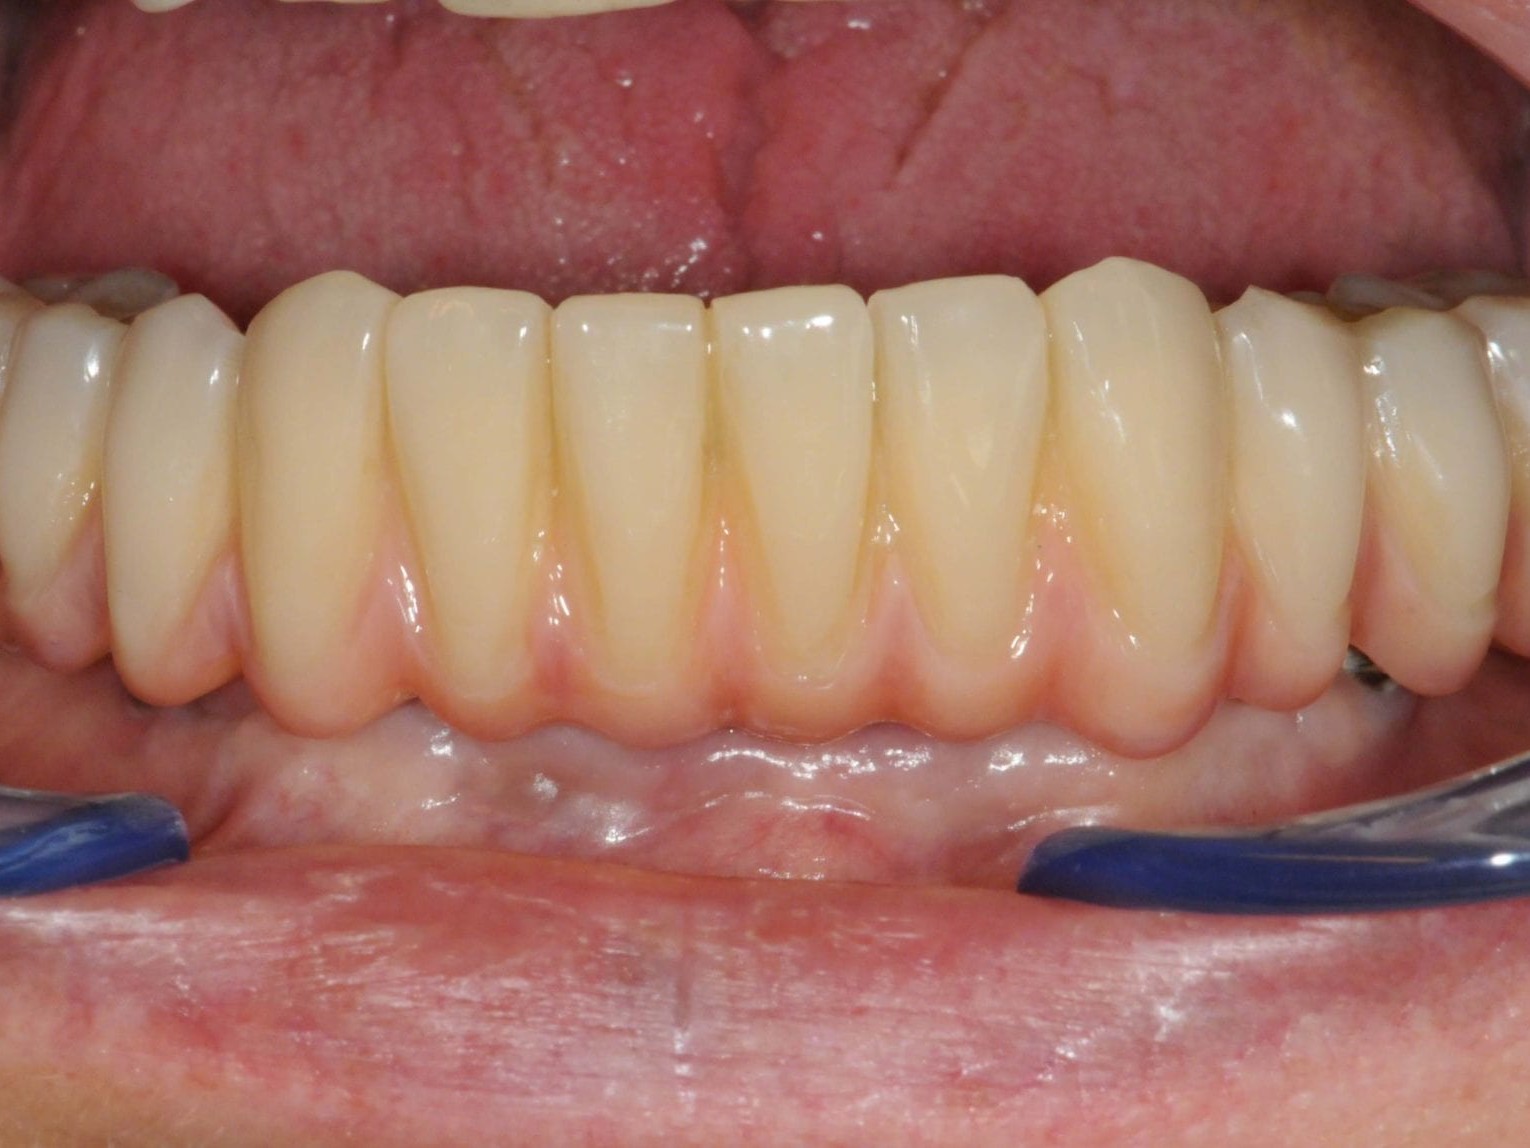

Wie weiter oben bereits beschrieben ist die Patientin im Oberkiefer mit einer keramisch verblendeten implantatgetragenen Brücke versorgt. Aus Sicht des Behandlungsteams schied daher eine keramische Verblendung des Unterkiefers aus. Die Verwendung von einem Composite mit keramischer Füllstruktur gewährleistet neben der notwendigen Farbstabilität und Plaqueresistenz zwei weitere Vorteile. Auf der einen Seite entsteht im Okklusionsmoment nicht das „keramische Klacken“ und zum anderen werden die auftretenden Kaukräfte gleichmäßiger auf das Implantat und den Knochen verteilt . Gerade bei implantologischen Oberkiefer- und Unterkieferversorgungen ist dieser „Stoßdämpfer–Effekt“ für den Langzeiterfolg wichtig. In dem vorliegenden Fall wurde die okklusal verschraubte Brücke aus einem massiven Titanblock gefräst (Abb. 4 und 5), wodurch das Endprodukt frei von aus der Gusstechnik bekannten Lunkern oder Verzügen ist. In Übereinstimmung mit den als Sheffield-Test ⁷ bekannten Kriterien der University of Sheffield, GB. ermöglicht dieser Fertigungsprozess gepaart mit der verblockten Abdrucknahme einen präzisen und somit spannungsfreien Sitz der Brücke – sowohl auf dem Meistermodell als auch im Munde des Patienten. Sowohl die Verblendungen der Zähne als auch des Zahnfleisches wurden unter Zuhilfenahme der diagnostischen Aufstellung mit visio.lign ⁸ im Labor angefertigt. Hierbei wurde besonderer Wert auf die naturgetreue Nachbildung der Rot-Weiß-Ästhetik und eine gute Hygienefähigkeit gelegt. Die Vorteile dieses Verblendsystems liegen in der exakten Umsetzung von der Aufstellung hin zur fertigen Arbeit durch mehrschichtige Verblendschalen (Abb. 6). Diese Verblendschalen werden schon bei der diagnostischen Aufstellung individualisiert und nach der Gerüstfertigstellung weiterverarbeitet. Mit passenden Individualisierungs- und Ergänzungsmassen sowie einem farblich abgestimmten Verbundsystem mit sehr guter Druck-Scheer-Festigkeit ⁹ ermöglicht dieses System durch Hinterlegen mit Intensivfarben das Gestalten von Mamelons ebenso wie die individuelle Gestaltung von Dentinleisten. (Abb. 7 und 8). Nach der zahntechnischen Erstellung der Unterkieferbrücke wurde diese intraoral inkorporiert (Abb. 9a). Die Implantatschrauben wurden mit 25 Ncm angezogen. Ein wichtiger Hinweis ist, dass hier stets das Originalequipment des Herstellers oder ein elektronisch kalibrierter Schraubendreher seine Anwendung finden sollte. Die Schraubenkamine wurden initial mit einem bakteriendichten, formstabilen lichthärtenden temporären Füllungsmaterial ¹⁰ verschlossen (Abb. 9b). Nach 6 Wochen werden die Implantatschrauben seitens des Prothetikers nochmals kontrolliert und ein abschließendes OPG erstellt (Abb. 10).